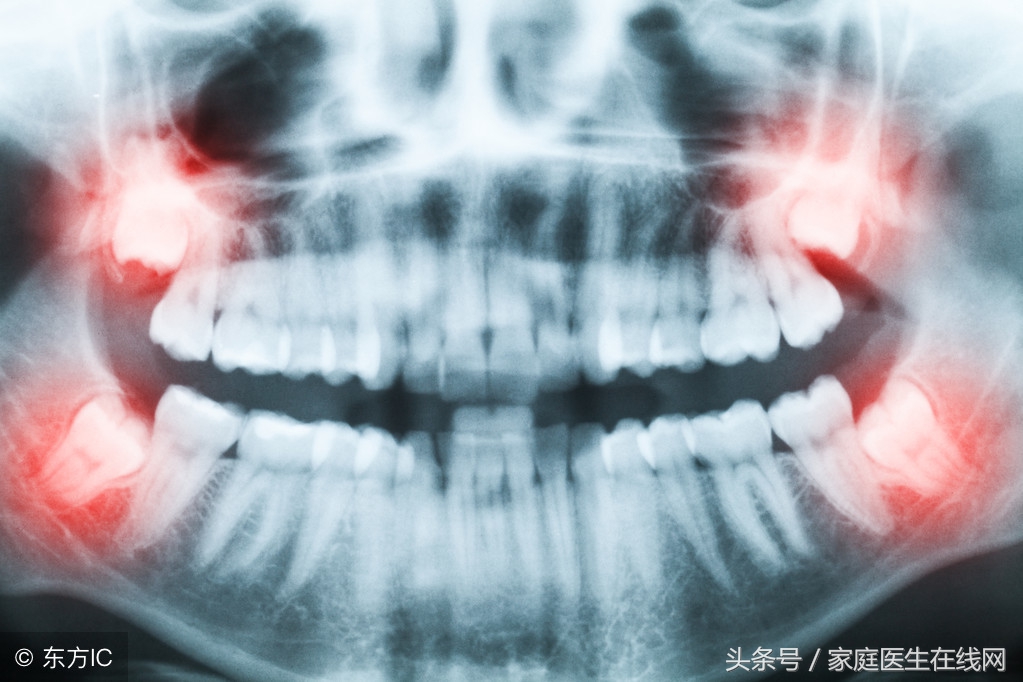

由于人類在進化的過程當中,食物也經過精細化的處理,在咀嚼食物時并不需要很大的咬合力,頜骨沒有足夠的刺激而越長越小,這時候智齒的生長就沒有足夠的空間,容易導致智齒生長方向發生變化,擠壓到其他的牙齒,造成牙齒疼痛的現象。

多數人在知道自己長了智齒之后會選擇去醫院進行拔出,想在智齒并沒有完全長成發生疼痛之前解決后患,這個方法其實是可行的。智齒沒有實際的咬合作用,而且在其生長的過程當中容易擠壓到其他牙齒,造成牙齒變形,甚至發生牙周炎的情況。